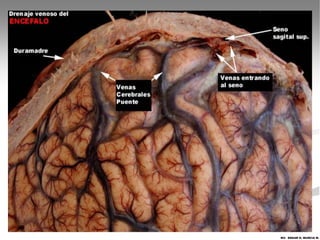

El lugar principal donde se resorbe el LCR son las

Vellosidades Aracnoideas en los senos venosos

dela duramadre.

El lugar principaldonde se resorbe el LCR son las Vellosidades Aracnoideas en los senos venosos dela duramadre. Dentro de las funciones del LCR junto con la meninges y el cráneo es proteger al encéfalo, actuando como almohadilla que amortigua los golpes sobre la cabeza. MV. EDGAR H. MURCIA M.